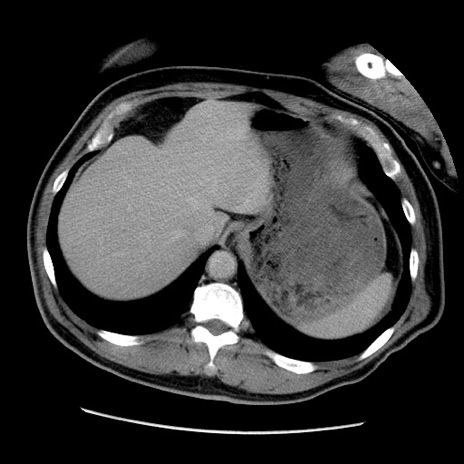

冠状断像